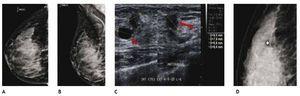

El CLI es de difícil diagnóstico en la mastografía, ya que su presentación más frecuente es como una tumoración con densidad similar al tejido mamario, generalmente sin microcalcificaciones o distorsión de la arquitectura en el 10% a 34%, seguido de asimetría en la densidad; otra de sus características relevantes y que lo hacen más agresivo en relación al cDi, es la mayor frecuencia de multicentricidad y bilateralidad, por lo que el ultrasonido juega un papel importante en el diagnóstico de esta variedad histológica (figs. 6A-D).

Figura 6 A) y B) Paciente asintomática de 44 años de edad. Tejido heterogéneamente denso, por lo que se recomienda ultrasonido. C) Quiste simple (flecha corta) y tumoración hipoecoica e irregular (flecha larga). D) Tumoración no identificada en la magnificación, BIRADS 4 C: cáncer lobulillar infiltrante.

La sensibilidad en la mastografía en el CLI tiene un rango del 75% al 81%, cabe mencionar que hasta en un 8% al 16% pueden encontrarse hallazgos benignos o un estudio normal; se ha reportado una tasa de falsos negativos mayor al 19%6.